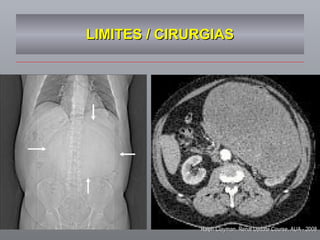

LIMITES / CIRURGIAS Ralph Clayman, Renal Update Course, AUA - 2008

AVANÇOS DE IMAGENS / ONCOLOGIA PESQUISANDO O TUMOR Limites estratégicos / precisão cirúrgica IRCAD